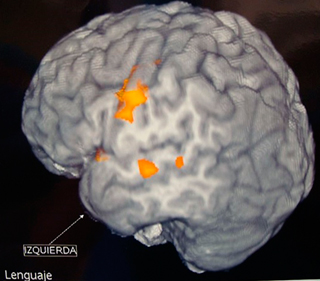

• En ocasiones es necesario estudios de resonancia magnética funcional, estudios de medicina nuclear como tomografía por emisión de positrones (PET –CT) o tomografía por emisión de fotón único (SPECT) e incluso estudios invasivos.